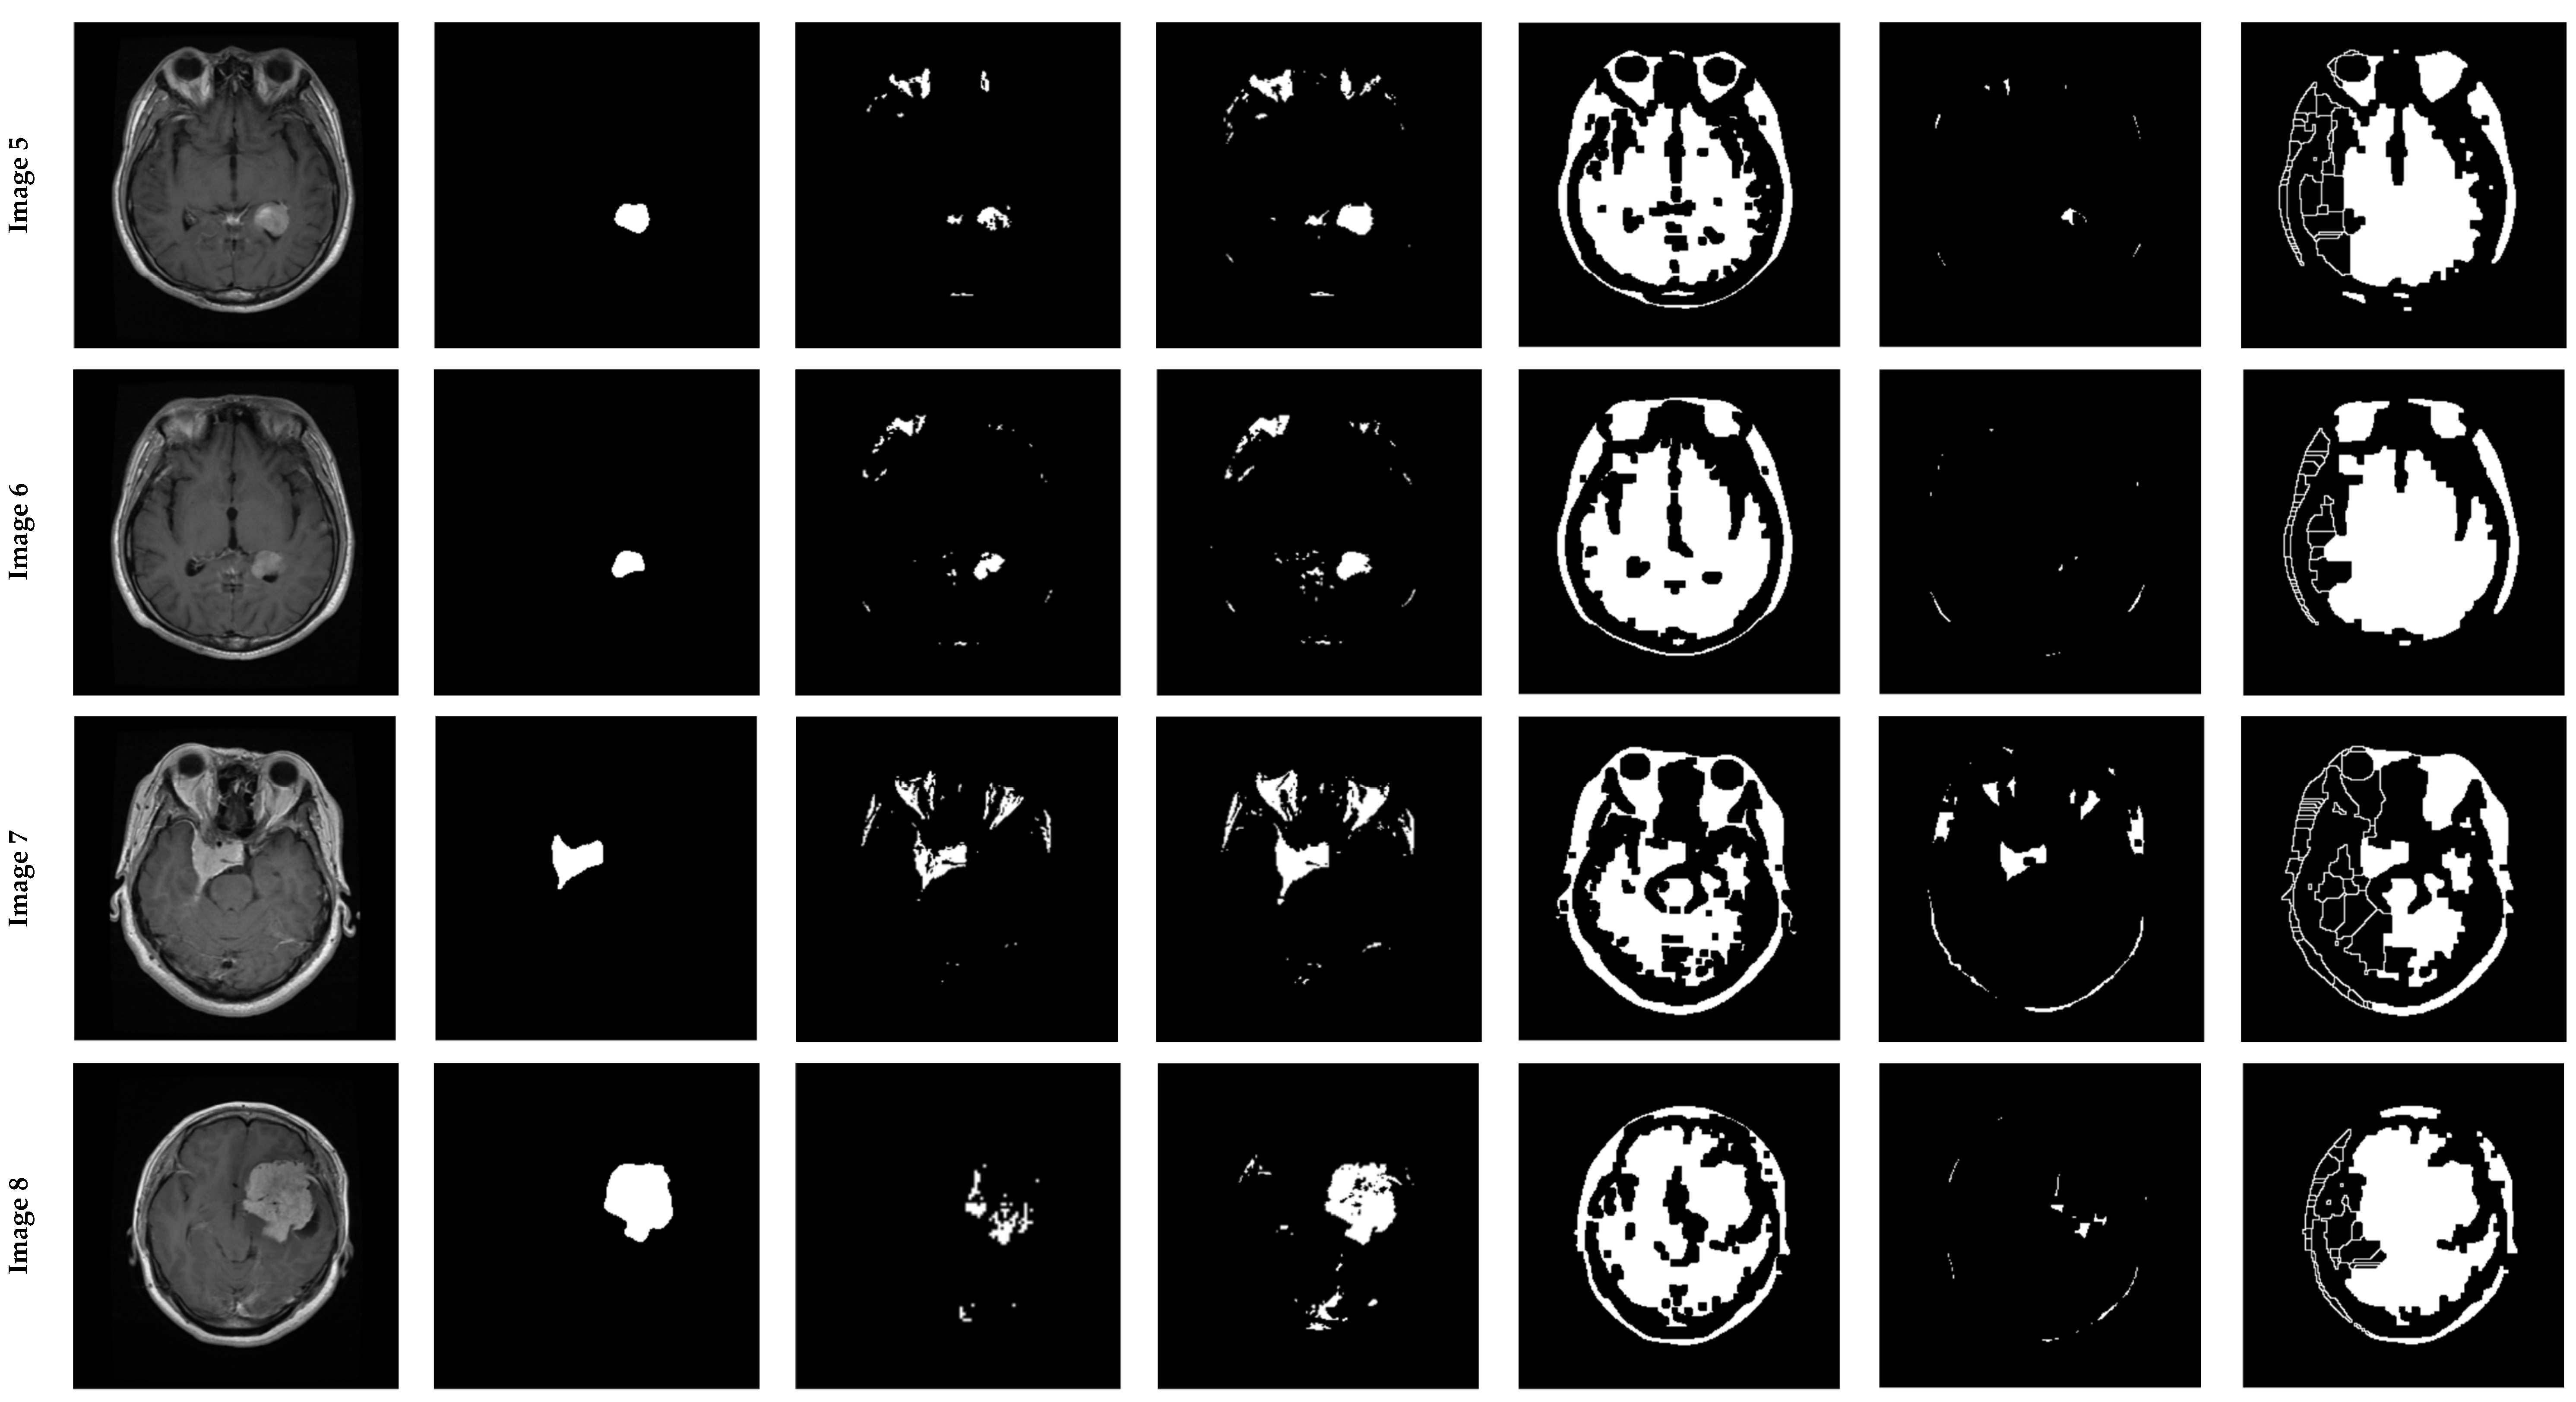

4.2. Experiments on the BraTS 2015 Database

4.2.1. Database Description

4.2.2. Experiments